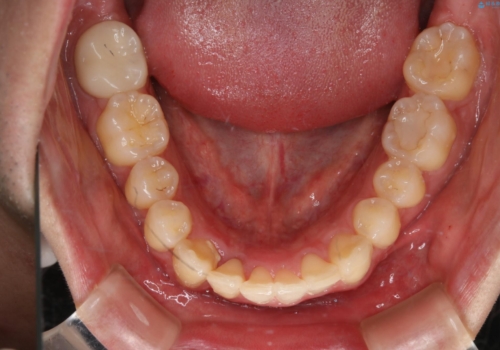

- 口元の突出感は気にならないが、上の前歯の角度と、下の前歯のがたつきが気になるとご相談にいらした方です。なるべく費用や治療期間を抑えて治療したいとのご希望に合わせて治療を計画しました。

この患者様への治療方針として、奥歯から少しずつ歯を移動させる方法と、歯をわずかに削って並べる方法とをご提案しました。短期間での治療を望まれたため、歯をサイズダウンさせて歯を並べました。わずかではあるものの、削った歯は元には戻せないことを十分ご説明し、ご理解ご了承を頂いた上で治療を行いました。